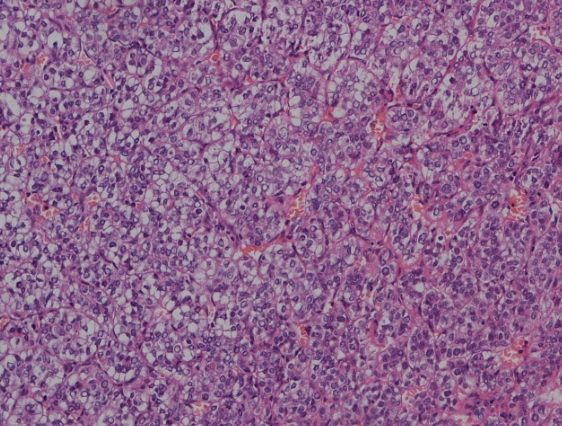

我記得醫生告訴我朋友,肝母細胞瘤的細胞看起來很原始,就像肝臟還沒發育好的樣子。這讓治療變得很棘手,因為它長得快,又容易復發。但好消息是,現代醫學進步,只要早期發現,治癒率不算低。